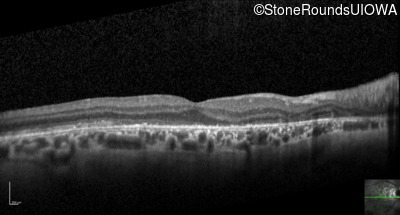

Optical Coherence Tomography - Right - 20/25 -2

Exemplar / OCT Stack